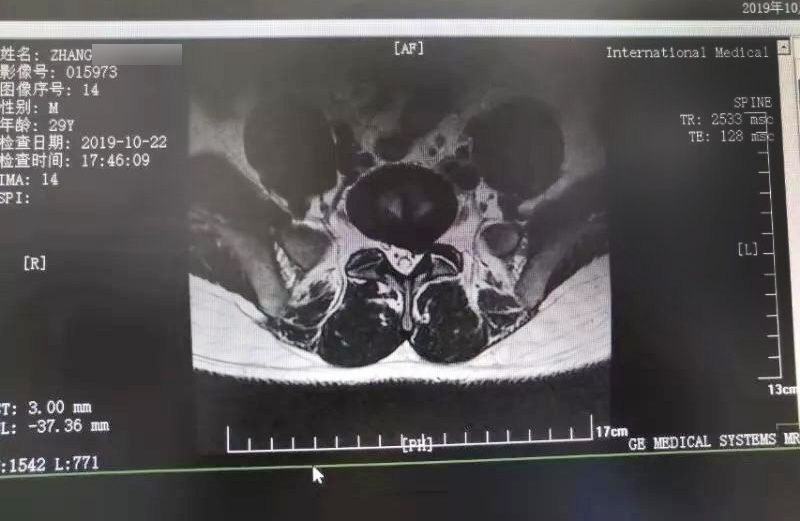

三秦網(wǎng)報(bào)道—西安國(guó)際醫(yī)學(xué)中心骨科醫(yī)院成功完成首例椎間孔鏡手術(shù)

三秦網(wǎng)報(bào)道—西安國(guó)際醫(yī)學(xué)中心骨科醫(yī)院成功完成首例椎間孔鏡手術(shù)。點(diǎn)擊閱讀。